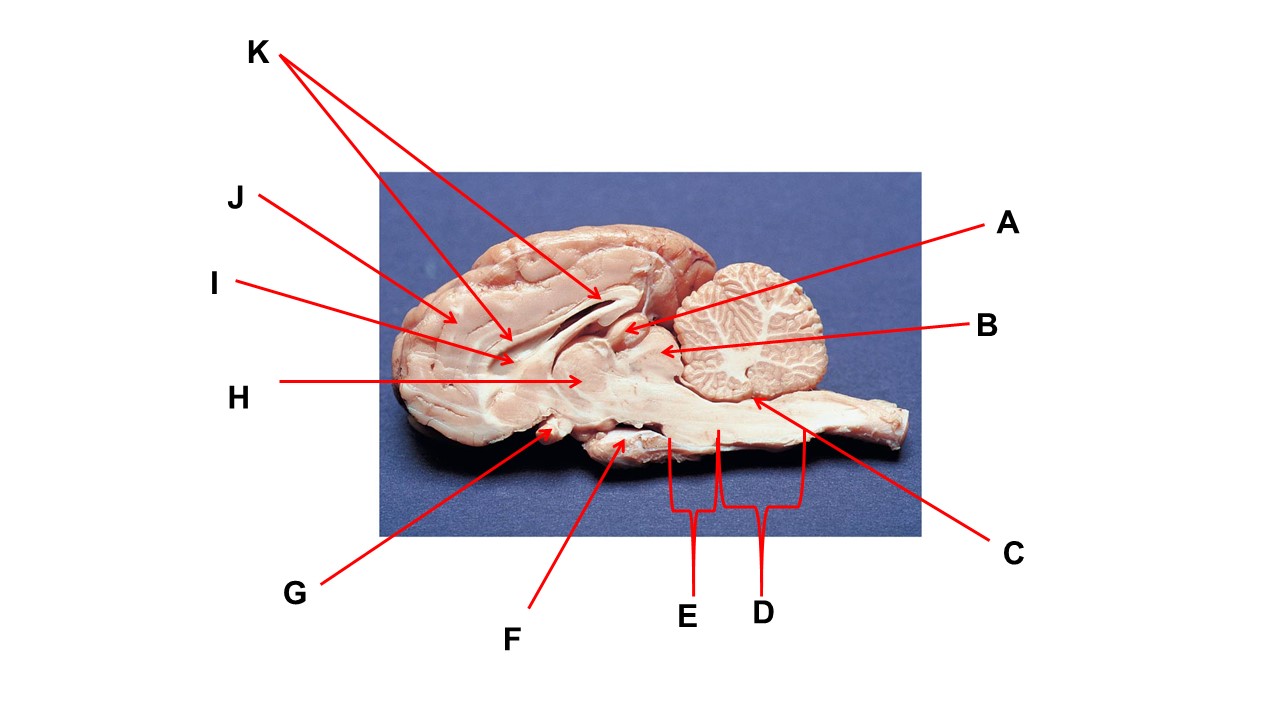

Name the structure at the tip of arrow A.

pineal gland

The cavity at the tip of arrow I is the _____.

lateral ventricular

The cavity at the tip of arrow I is filled with ______.

cerebrospinal fluid

Name the structure at the tip of arrow F

mammillary body

Name the structure at the tip of arrow A.

pineal gland

Name the structure at the tip of arrow G

optic chiasma

Name the nerve at the tip of arrow H.

optic